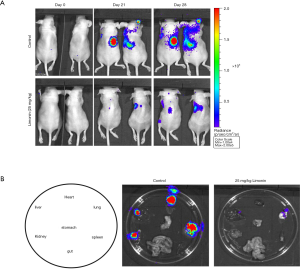

The mouse left ventricle injection tumor metastasis model was used to further investigate the inhibitory effects of limonin on mammary tumor metastasis. One week prior to the injection of MDA-MB-231 cells, the mice were injected intraperitoneally with vehicle or limonin at 25 mg/kg/day. The luciferase-labelled MDA-MB-231 mammary tumor cells metastasized to the lung area following 21 days in the control mice (Figure 5A). By contrast, treatment with limonin for 28 days significantly inhibited MDA-MB-231 cell lung metastases in the limonin-treated group (Figure 5A). The images were obtained from the typical metastatic target organs (lung, heart, kidney, stomach, spleen, liver and gut) (Figure 5B). The results revealed that limonin treatment significantly reduced the metastatic node numbers in the target organs, indicating that this compound could act in a preventive mode of action.